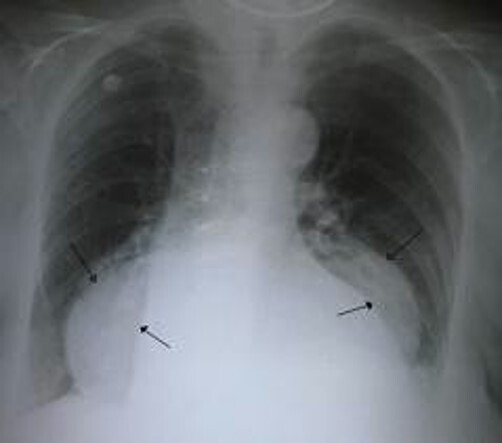

hiatal hernia

A

-A hiatal hernia occurs when the upper part of the stomach, which is joined to the esophagus moves up into the chest through the diaphragm.

-It is common and occurs in about 10% of pts

-SX:

-heartburn

-sudden regurgitation

-belching

-pain on swallowing hot fluids

-feeling a food sticking in the esophagus

-MC in overweight middle-aged women and elderly people.

-It can occur during pregnancy.

-dx confirmed by barium swallow, radiographs or endoscopy.